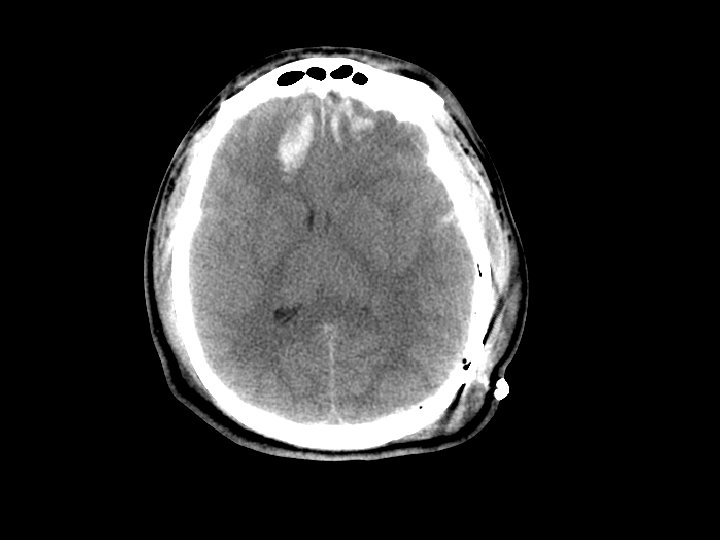

Subdural Hematoma (SDH) • Hemorrhage between the dura and the brain – More common than EDH – 30% of patients with TBI have a SDH • CT: Crescent shaped area of blood • Can be acute, subacute or chronic – Subacute or chronic presents days/weeks after injury

Subdural Hematoma (SDH) • Elderly at risk (less severe mechanisms) – Brain shrinks with age resulting in stretching of the bridging veins in the subdural space • May gradually enlarge (slower than EDH) • Surgical drainage for lesions resulting in masse effect and shift